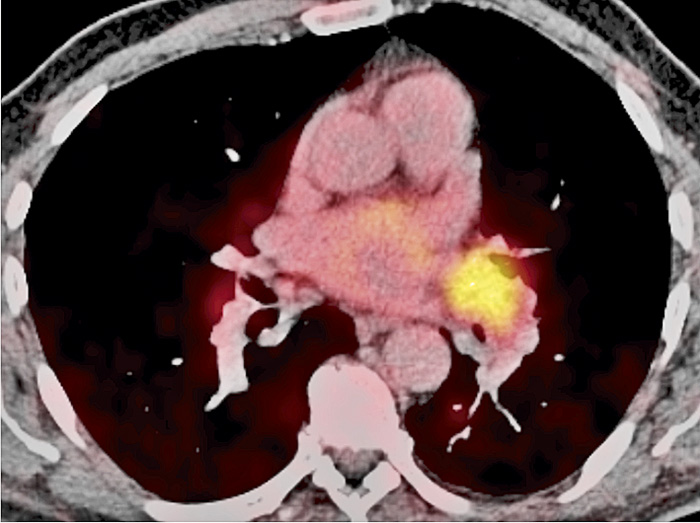

Figur 1C.  Tvärsnitt från PET/DT med FDG som visar lymfkörtelförstoring i vänster lunghilus med ett kraftigt ökat spårämnesupptag.

Figur 2A. 69-årig man med lungförändringar orsakade av tularemi (Fall 2). Tvärsnitt från datortomografi som visar en förtätning i vänster ovanlob, lingulasegmentet.

Figur 2B. Koronart snitt från PET/DT med FDG som visar spårämnesupptag i lungförtätningen och massivt upptag i mediastinala lymfkörtlar.

Kombinerad undersökning med PET och DT visade FDG-upptag både i den misstänkta tumören och i mediastinala lymfkörtlar. Infiltratet hade dock minskat något jämfört med föregående datortomografi, och bronkoskopi visade enbart makro- och mikroskopisk inflammation. Senare framkom att patienten haft en feberepisod ett par veckor innan han sökt läkare, men han var nu feberfri. Serologi för tularemi blev starkt positiv, och förändringarna läkte successivt ut helt.